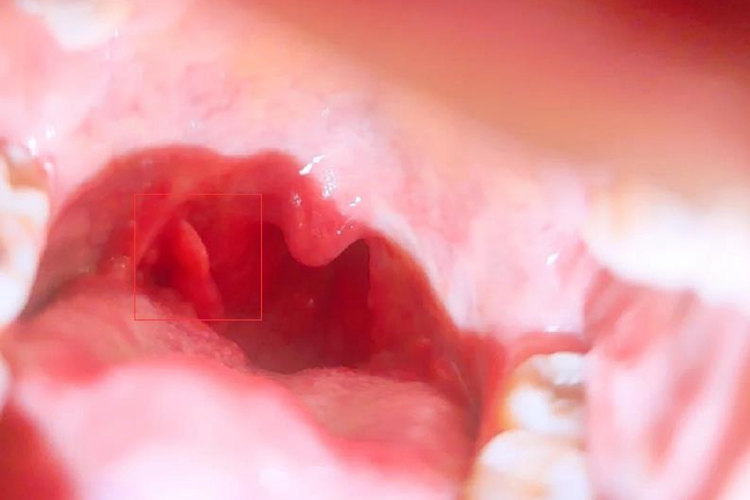

扁桃体术后肉芽组织增生是术后正常的表现,会在手术的创面出现凹凸不平的增生组织,可呈鲜红色,柔软湿润,形似鲜嫩的肉芽。

扁桃体术后肉芽组织增生是由于机体对手术创面的自我修复造成,若产生的肉芽组织较少,属于正常现象,若产生的肉芽组织较多,可能是由于创口较大或局部感染造成。

若产生的肉芽组织较少,为创面瘢痕,不需要特殊处理,完全愈合后一般不会产生异常影响。若产生的肉芽组织较多,已经影响吞咽,需就医进行切除治疗。